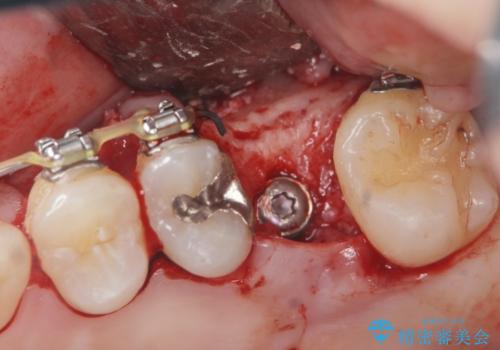

- 他院での矯正治療中、欠損した左上奥歯のインプラント治療を希望され来院されました。

最終的な歯の位置を矯正の担当医と綿密に相談しながら、インプラントの埋入部位を決定し治療にあたりました。

骨量が少なかったことから、上顎洞内へのソケットリフト方をインプラント埋入と同時に施行しています。